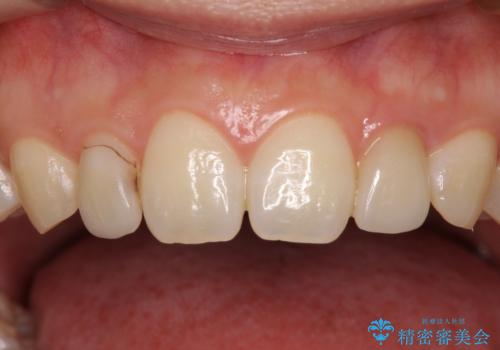

- ラミネートベニアと歯の境目の着色を気にして来院された患者様です。

矯正治療後に矮小歯であった歯をラミネートベニアにて形を変えたそうですが、矯正歯科治療直後であったためか、歯肉の位置が変わったことで境目が見えていました。